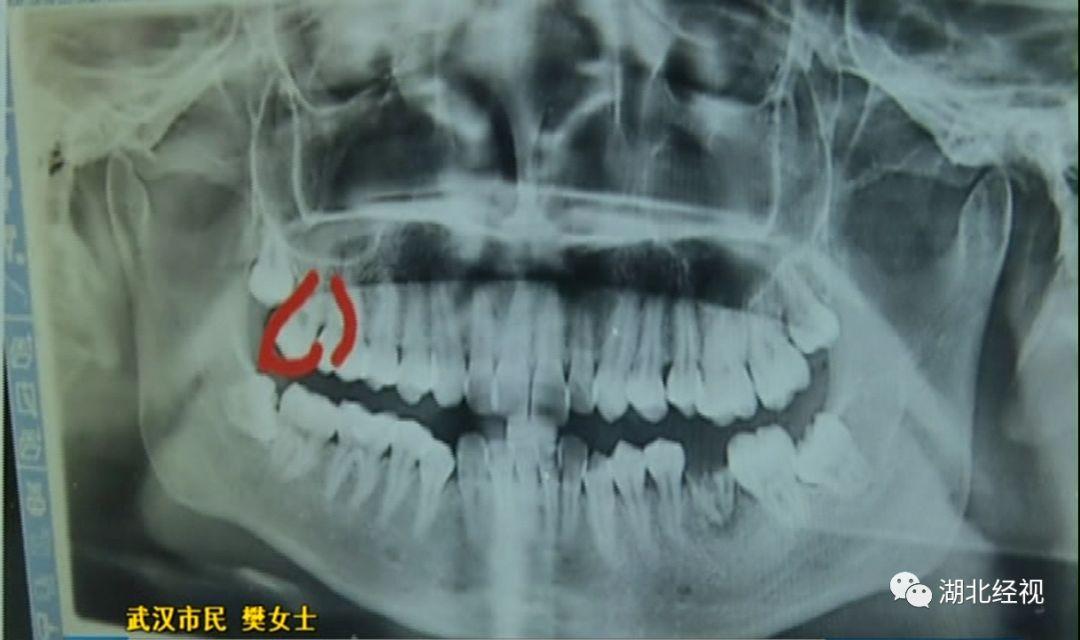

拔智齒旁邊的好牙沒了

樊女士說,拔牙時(shí)上了麻醉,嘴巴里都是麻的也沒有感覺。但回家一個(gè)星期后照鏡子,突然發(fā)現(xiàn)自己的一顆好牙沒有了,一顆好牙齒被這樣被拔掉了。

原本是準(zhǔn)備拔掉多余的牙齒,但醫(yī)生卻意外拔掉了一顆好牙,這讓樊女士痛心不已。